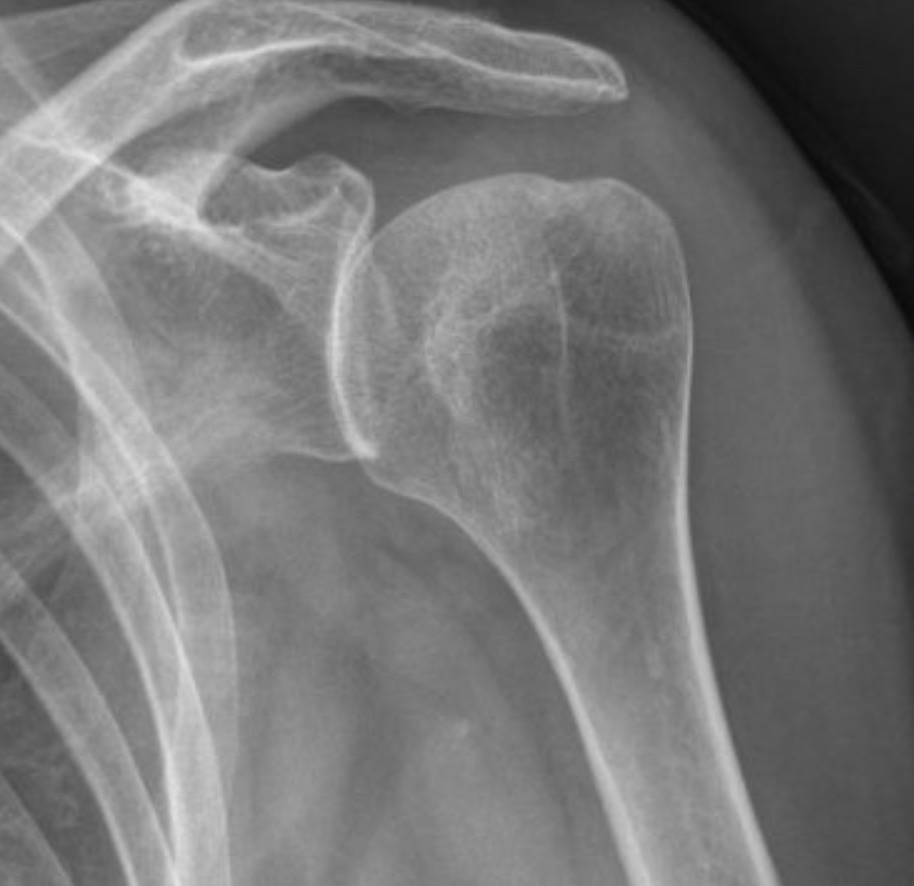

Luxation antérieure

de l'épaule

À l’imagerie, sur une radiographie de face, on note une superposition de la tête humérale et de la glène de l’omoplate.

Sur une radiographie de profil, la luxation est évidente avec une tête située en arrière de la glène.